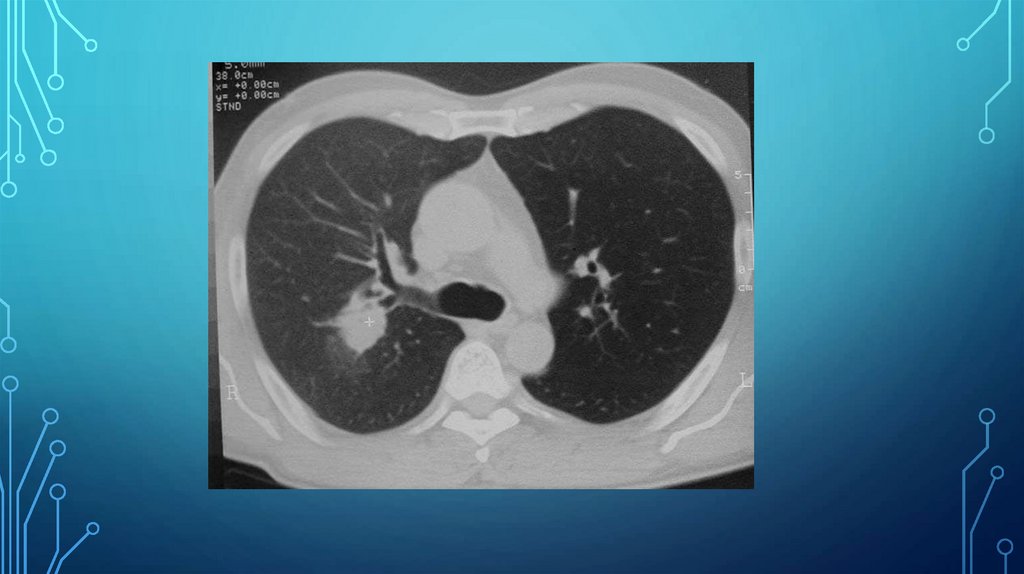

Рис. 29. Туберкулома верхней доли правого легкого.